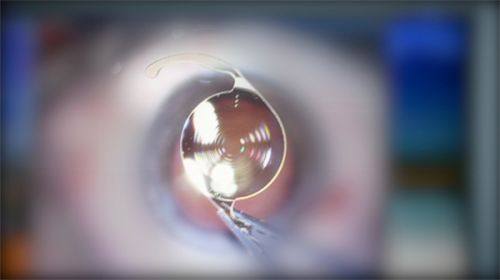

2. 比如它较早引进飞秒白内障设备技术并开展此项手术。飞秒白内障手术比传统的白内障手术更精细、更安心,能让患者修复得更快。